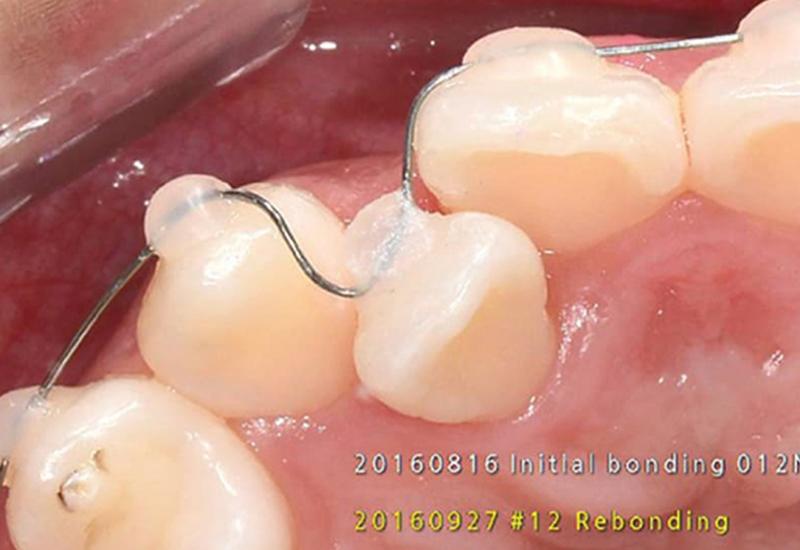

歯の表面に「ブラケット」と呼ばれる四角い突起物をつけず、極薄のチューブと白いレジン(プラスチック) を用いて、白~透明なワイヤーを固定する「ブラケットフリー矯正」と呼ばれます。

ワイヤーの「歯を動かすスピード」と、マウスピースの「目立ちにくさ」の良いとこ取りを目指した治療法です。

最大の利点は、「歯までの距離」です。

歯の表面ギリギリにワイヤーを通すことで、歯を動かすためのポイントに直接力が伝わるため、従来の約半分程度の期間で治療が完了するケースも珍しくありません。

歯の表面に透明な装置がつきますが、金属ワイヤーより目立ちにくいです。

取り外しはできません。アライナー矯正の前後で併用することがあります。

※当院では、マウスピース矯正とアラインチューブ矯正を併用した際の追加費用はかかりません。